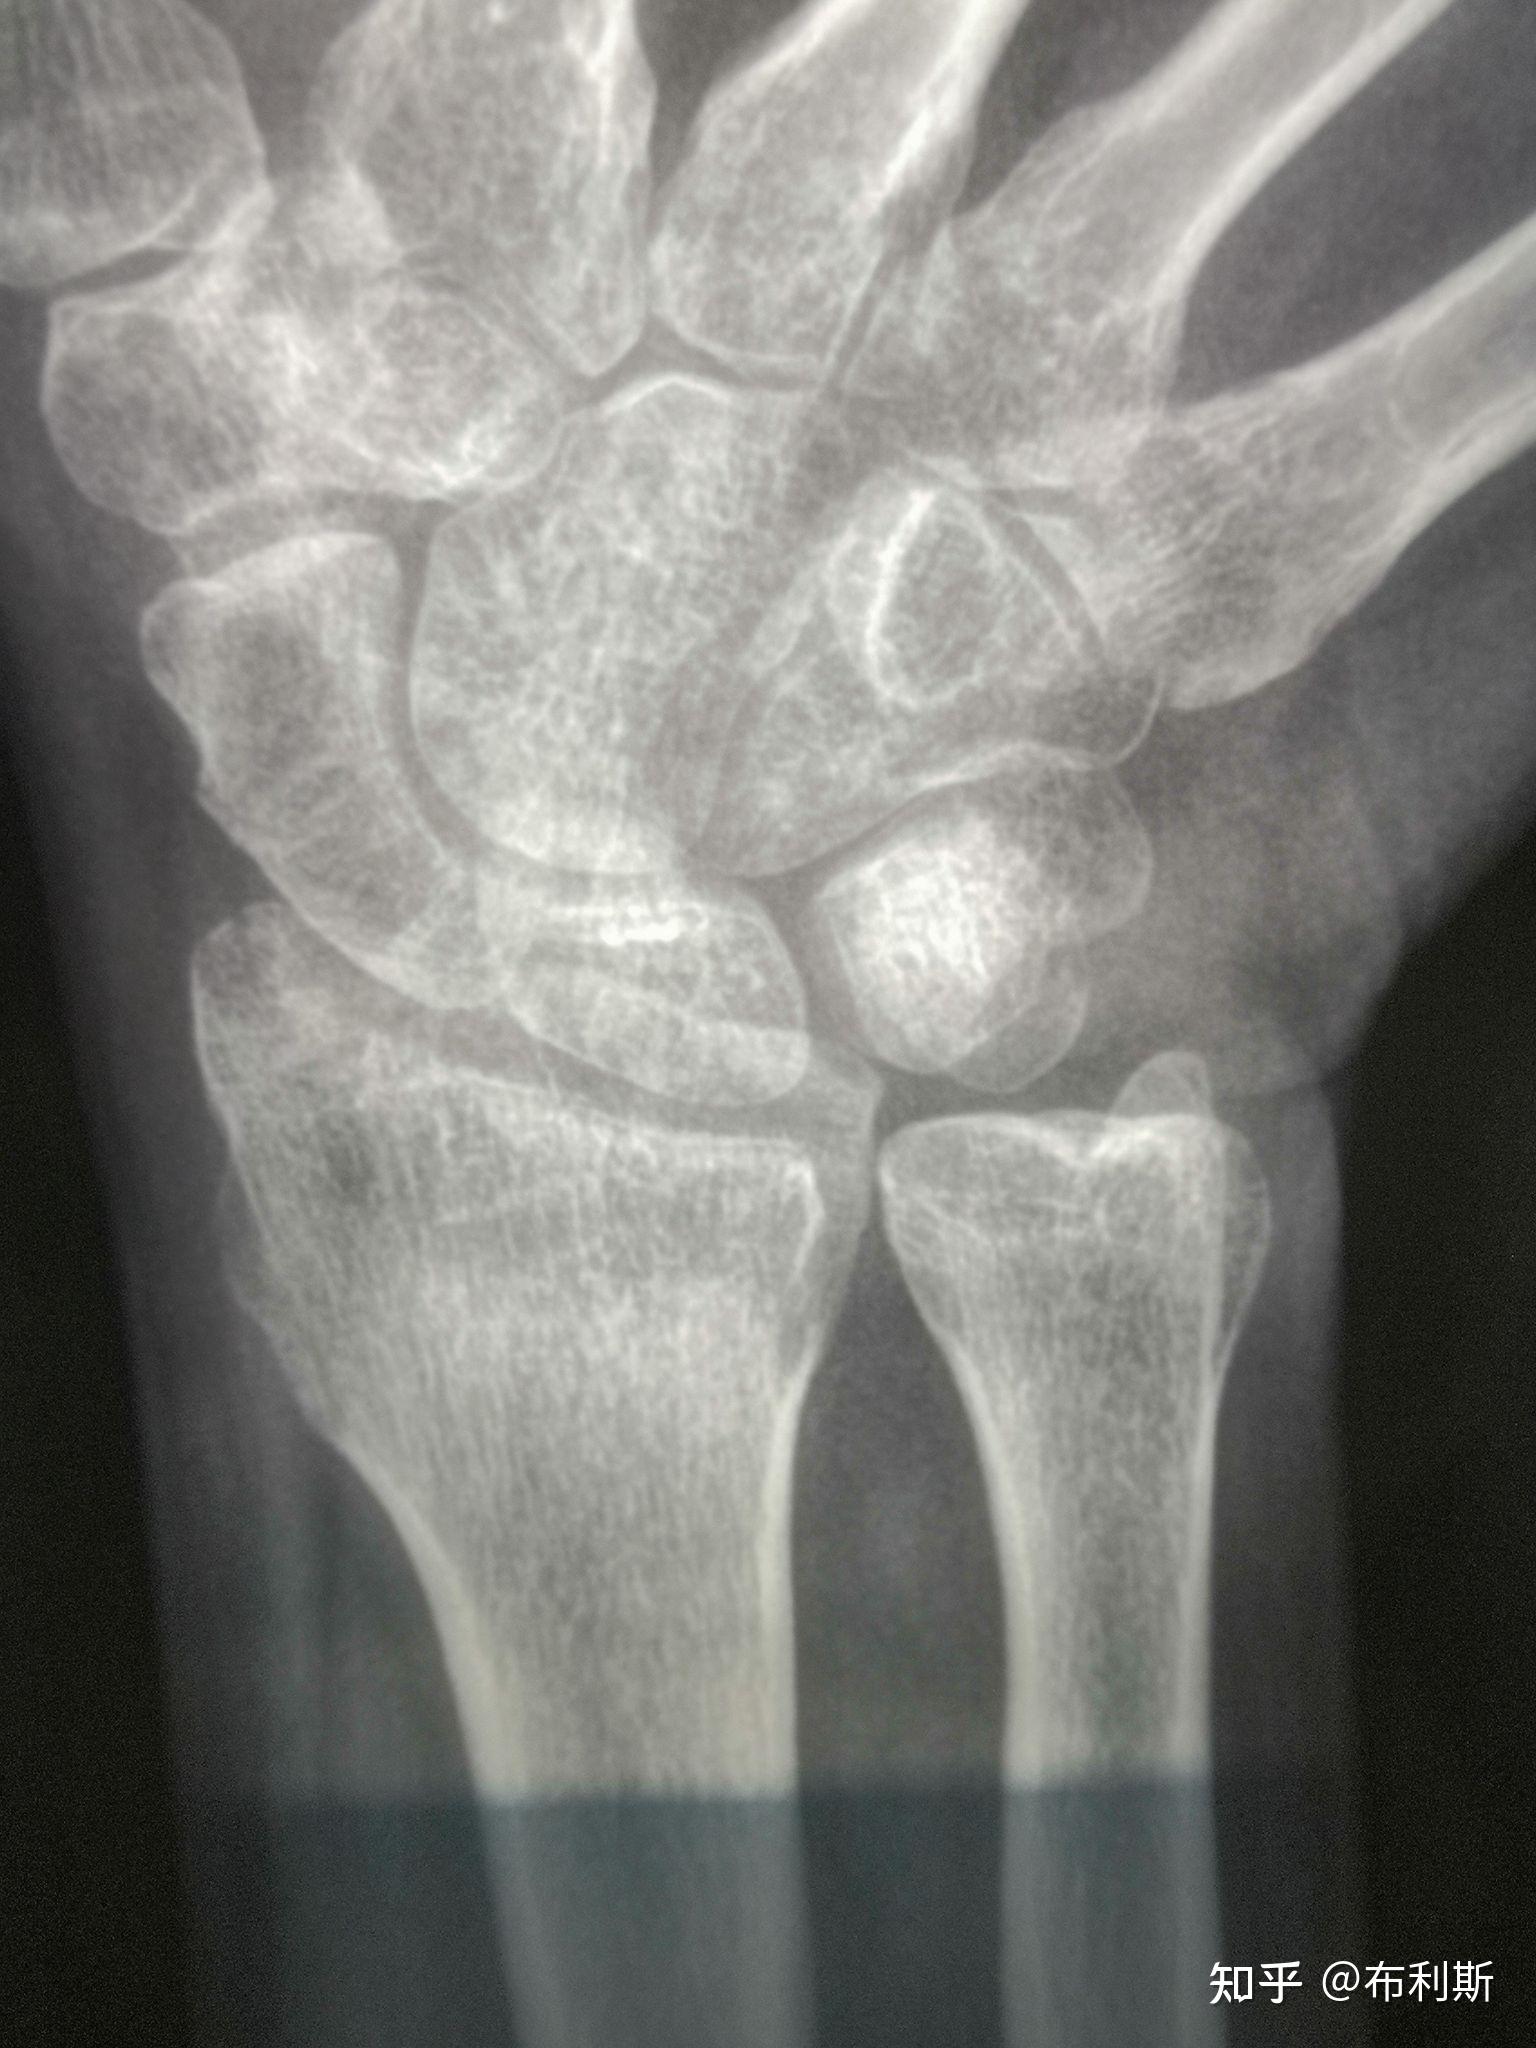

腕舟骨骨折

左手手腕舟骨骨折,这受伤程度严重吗?目前已夹板固定敷药8天.

手腕舟骨骨折经历

左手舟状骨骨折